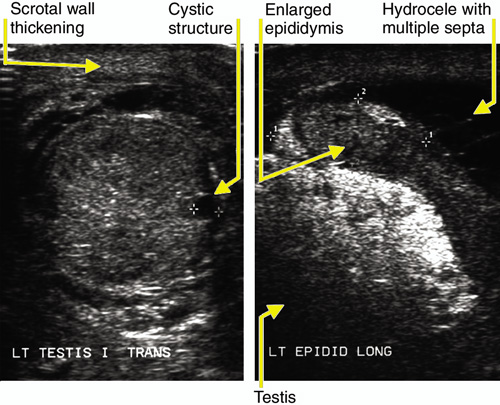

2: Scrotal ultrasound images

Left: Transverse image of the enlarged left testis (4.5 x 3 x 2 cm), with non-homogeneous echotexture and several small, rounded, echolucent cystic structures within the testis measuring 3 mm in diameter. The right testis showed similar, but less severe, features.

Right: Longitudinal image of the enlarged left epididymis.